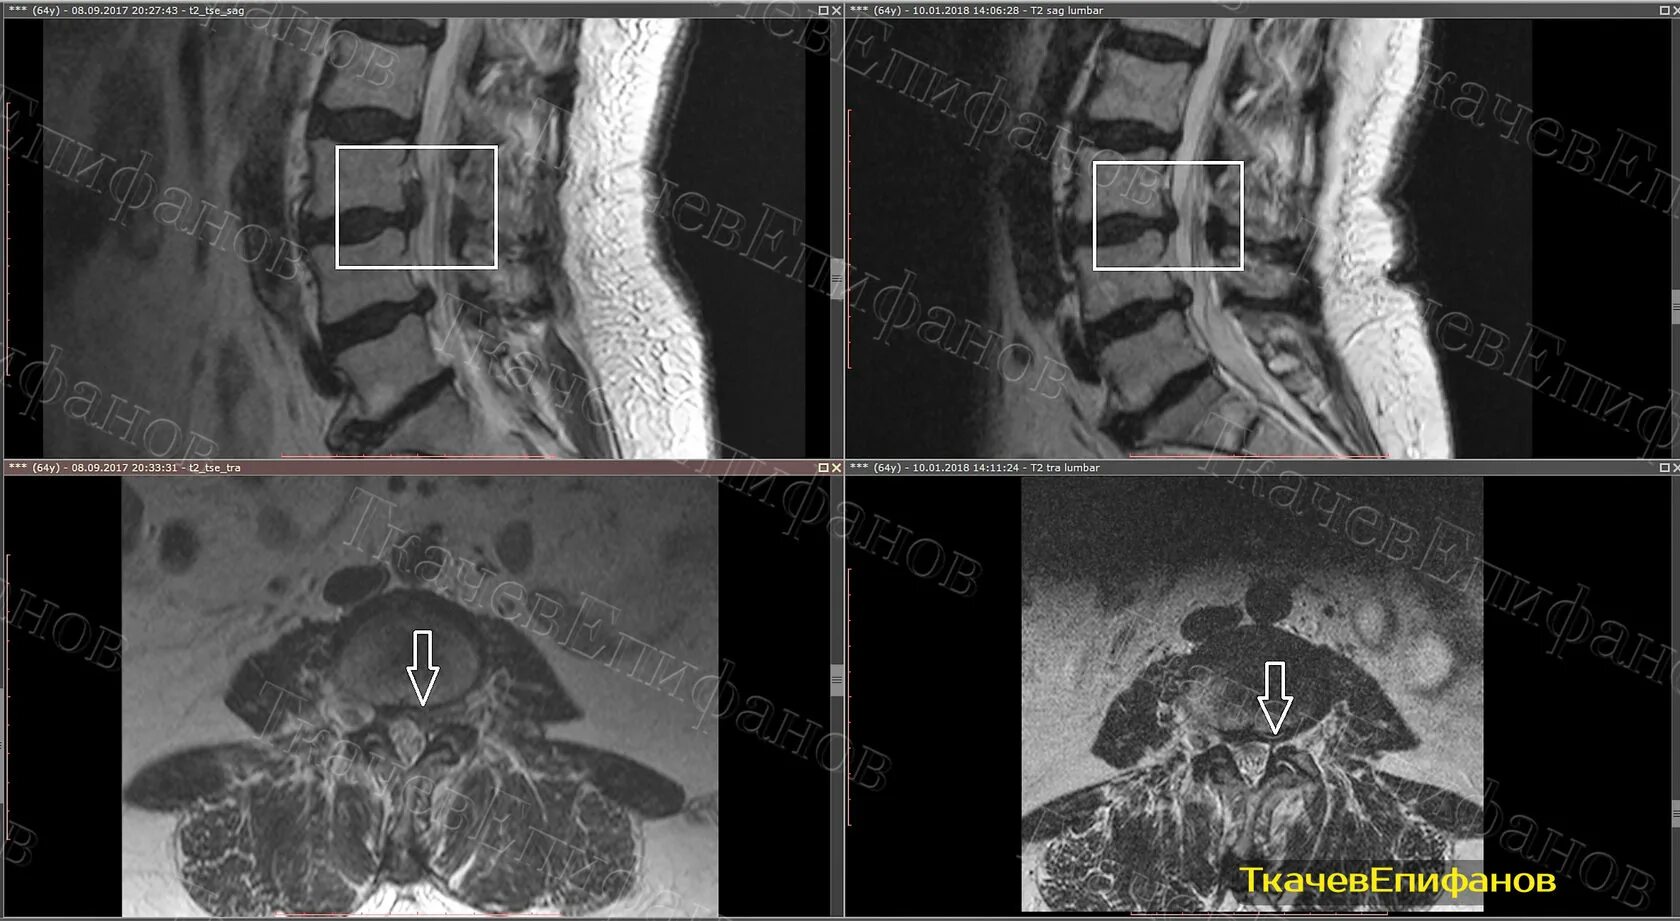

Мрт 8